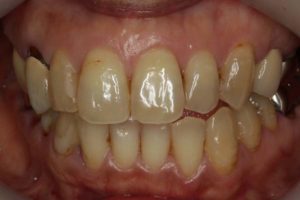

最後に、術前・術後のお写真をご紹介します。

院長のコメント 1年間お疲れさまでした。たくさん治療しましたが、「あっけなくおわりました。」とおっしゃって頂きありがとうございました。当院ではお一人1時間でお約束をお取りしていますので、20分や30分で細かく分けて治療するのに比べ、無駄がなく効率よく進みます。 さらに、治療用の椅子は1台(メインテナンス用の椅子がもう1台)しか置いていませんので、私はお一人の治療に1時間集中できますから、なおさら治療は進みます。 ただ、決して急いでいる訳ではなく、じっくり治療をしているのですが、一つ一つ確実にステップを踏むとミスが少なくなり、その結果治療も早く進んでいくのです。 さて、この患者さんは、ブリッジをやり直す時にそのままブリッジにするかインプラントにするかとても迷われていたのですが、最終的にはインプラントを選択されました。アンケートにもありますように、皆さんが考えている程インプラント治療は痛みを伴うものではありません。今回のケースでも、全く痛みはなく痛み止めを飲むこともなかったそうです。